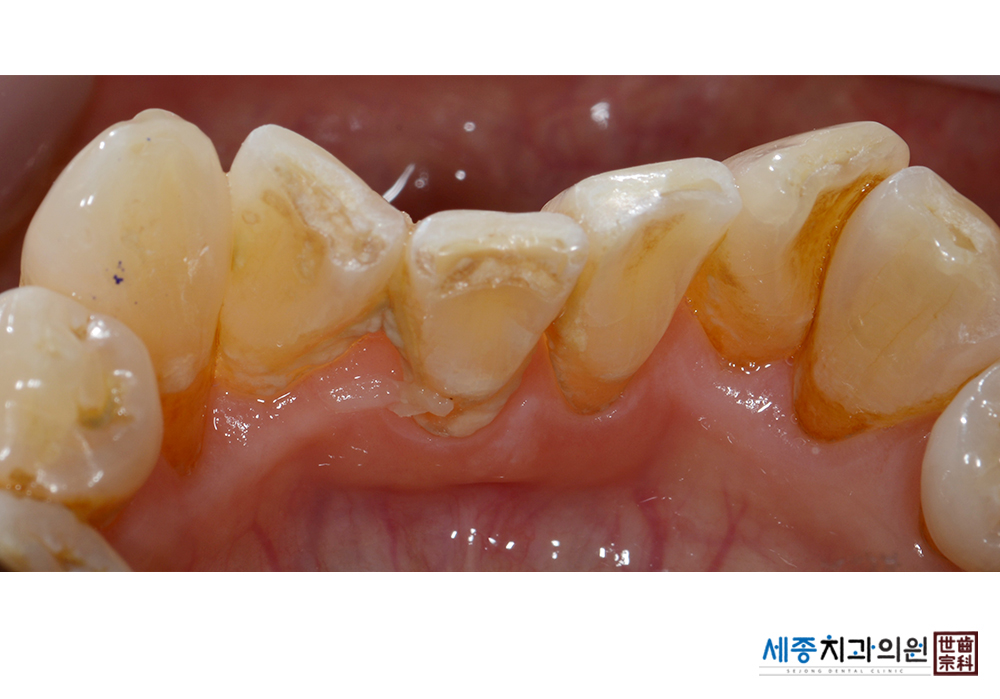

[스케일링] 치주질환 예방 스케일링

치료후 : 2021-05-13

가글마취&저주파 스켈러를 사용한 스케일링